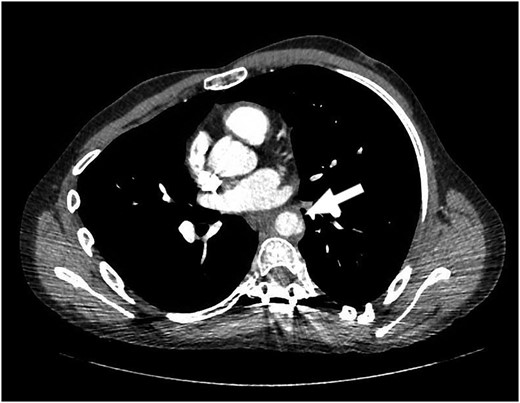

Our patient is a 24-year-old male with the EDS type VI who had undergone rod fixation of his spine for scoliosis, ocular surgery for a ruptured globe and ligation of his popliteal artery after an attempt was made to repair his aneurysm. The patient was being followed at Duke EDS Clinic where he underwent an extensive workup, and a definitive diagnosis was established. He presented to the emergency room (ER) after being kicked in the abdomen during a martial arts class. The patient felt an instant abdominal pain which resolved quickly. The patient went home after the incident and then developed nausea, vomiting and diaphoresis. He was hemodynamically normal in the ER. His groin pulses were slightly diminished compared with his radial pulses. The patient underwent a computed tomography (CT) scan of the chest, abdomen and pelvis with intravenous contrast. The patient was found to have traumatic aortic injury (Fig. 1). Cardiovascular surgery was consulted. The patient was admitted to the ICU for nonoperative therapy. He was started on Esmolol intravenously, and Diltiazem was added in order to keep his mean arterial pressure around 60. After 2 days in the ICU, the patient was transitioned to medications by mouth. He was allowed to ambulate on the fourth day and discharged on the eighth day after a long discussion with him and his family.